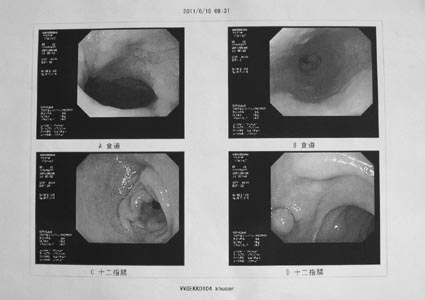

2)上部内視鏡

十二指腸にポリープ在り、その他異常なし

<所見> 上部臓器に問題個所はなし